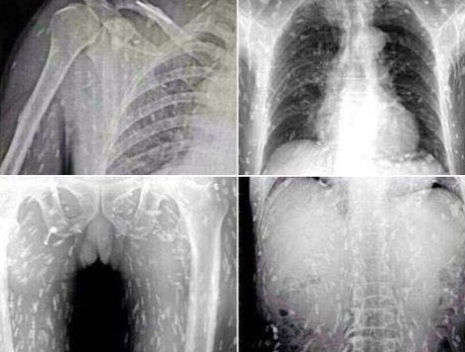

Galenos de un hospital de la provincia de Guangdong, se llevaron una gran sorpresa al descubrir que un habitante de dicha localidad estaba infestado de larvas, esto luego que consumió sushi y sashimi, hechos con un pescado repleto de larvas microscópicas, las cuales se alojaron en el interior de su cuerpo.

Se conoce, que el hombre cuya identidad se mantiene en reserva, acudió al centro médico debido a que tenía fuertes dolores estomacales y bastante comezón en el cuerpo.

En el hospital los médicos confirmaron que ello a que el sujeto comió pescado crudo contaminado, y sino hubiese sido atendido a tiempo, estas larvas pudieron devorar sus órganos.